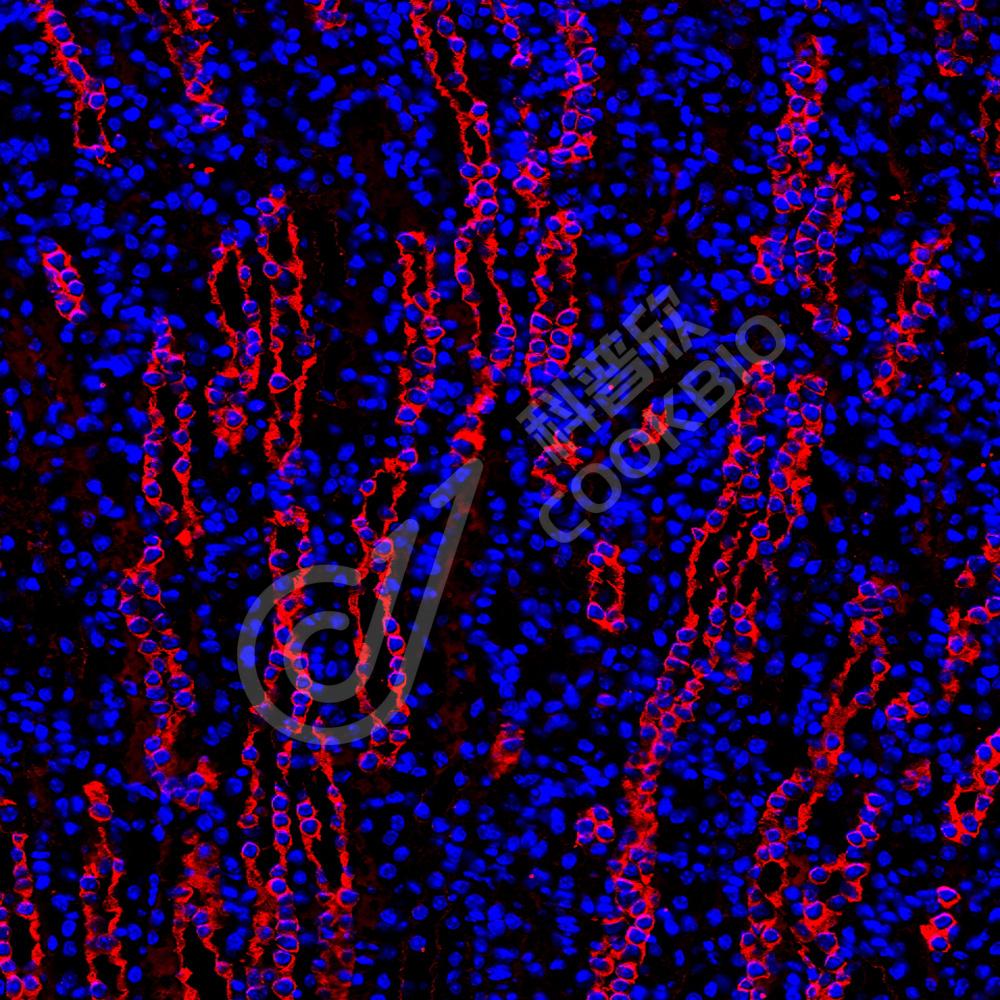

IF检测non-muscle Myosin IIB/MYH10蛋白(货号 K2363561)(红色).

样品: 人乳腺癌, 4%多聚甲醛 (货号KSG1101) 固定12-24小时.

抗原修复: 柠檬酸抗原修复液(干粉, pH 6.0) (KSG1201), 高压锅均匀喷气计时2分钟.

封闭: 3% BSA(货号KSGC305010)的PBS溶液, 室温孵育30分钟.

—抗: 1: 2300稀释, 4℃ 孵育过夜.

二抗: Cy3标记山羊抗小鼠IgG (H+L) (货号KB63903), 1: 300稀释, 室温孵育1小时.

样品: 小鼠肾, 4%多聚甲醛 (货号KSG1101) 固定12-24小时.